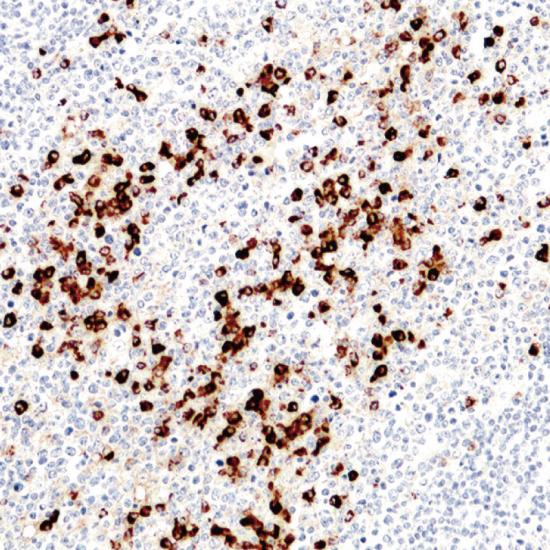

Lamdba Light Chain

此抗體和人免疫球蛋白的Lambda鏈反應(yīng),和Kappa鏈無交叉反應(yīng),可標記帶有Lambda鏈的B淋巴細胞、漿細胞和免疫母細胞,細胞外的免疫球蛋白Lambda鏈也可著色,應(yīng)注意區(qū)分。主要用于淋巴瘤和淋巴結(jié)反應(yīng)性增生的鑒別診斷。